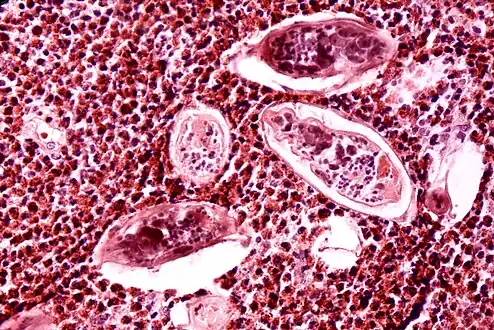

-

Ultrasonographic images in hepatic schistosomiasis -

High-powered detailed micrograph of Schistosoma parasite eggs in human bladder tissue -

S. japonicum eggs in hepatic portal tract